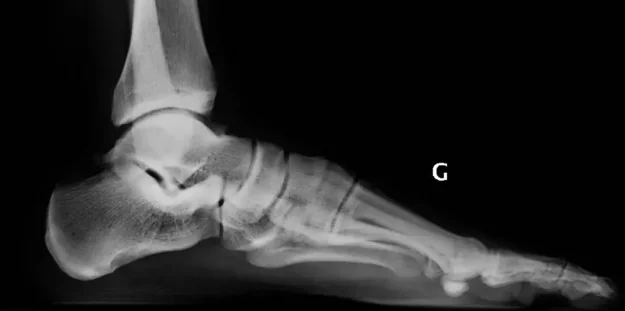

Le symptôme douloureux est le principal motif de consultation pour nos patients. Le pied est une zone anatomique soumise à des fortes contraintes, susceptible d’être le siège de nombreuses douleurs.